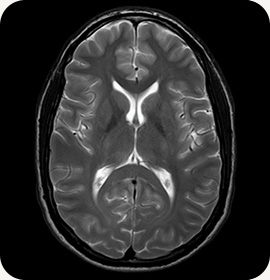

MRI(磁共振成像)是利用强磁场获取人体图像的先进成像检查技术。患者进入大型圆柱形磁体后,设备会发出射频脉冲。MRI 利用人体各部位氢原子核的共振现象,通过测量和分析共振后发出的信号,获取影像信息。因此,能够获取有关肌肉、软骨、血管和神经的详细信息。

可根据不同疾病和身体部位进行定制成像检查。根据特斯拉值(表示磁场强度)不同,检查时间和分辨率也会有所变化,但更高的特斯拉值并不一定代表更好的设备,而是需要根据具体需求选择合适的设备。

最新款飞利浦 MR 设备 Ingenia 3.0T CX Quasar 系统采用飞利浦独创的 MR 技术, |

飞利浦 Achieva 1.5T 具有高信噪比,可生成高分辨率影像, |

配备快速精确 MRI 的成像中心

在 MRI 扫描之前,需要考虑多种因素,即设备是否为新设备,价格是否合理,读片是否准确,以及是否需要等待较长时间等…… Mint 医院影像中心配备了最新型号的设备(截至 2018 年 9 月), 满足了患者的需求。此外,我们还建立了专门的门诊服务系统,能够进行预约管理,并针对两台不同 MRI 设备配备了高效的操作系统,实现一站式检查和咨询,无需长时间等待。